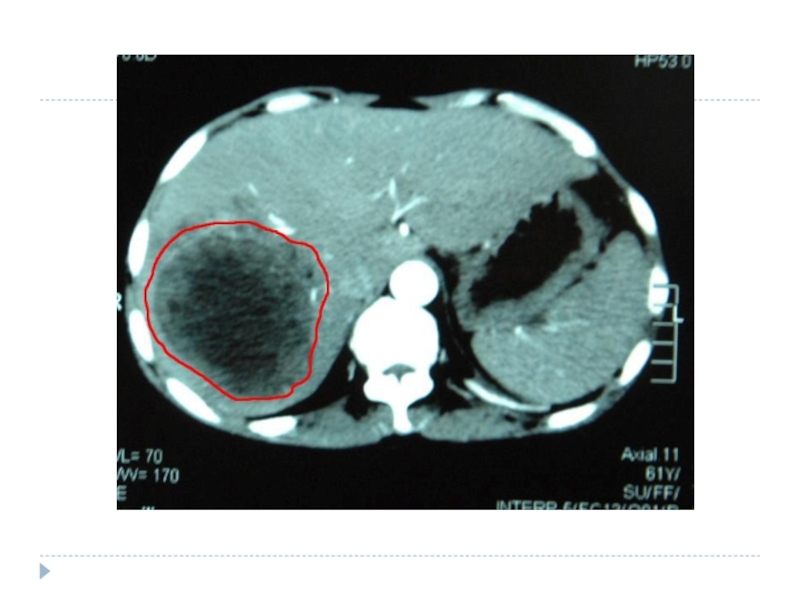

Ультразвуковое исследование (УЗИ) позволяет обнаружить опухоль и в некоторых случаях определить ее тип.

Обязательные методы исследования Ультросонография + прицельная аспирационная тонкоигольная биопсия. Ангиографию печени выполняют после введения контрастного вещества в чревной ствол; Компьютерная томография; Ядерно-магнитный резонанс

Компьютерная томография (КТ) очень эффективна при диагностике опухолей печени, позволяет обнаружить даже маленькие новообразования, незаметные на УЗИ. В ЛIСОД для улучшения изображения проводится КТ с контрастированием – внутривенно вводится контрастное вещество, что дает возможность специалистам изучить расположение сосудов в печени. Во время компьютерной томографии аппарат получает изображение тонких срезов, что позволяет специалистам тщательно обследовать структуру органа и выявить даже небольшие опухоли.